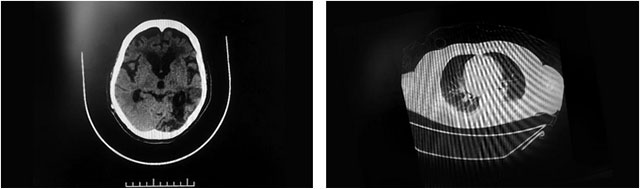

▲ 患者多发性脑梗,且肺部感染严重

7月23日,顾女士再次突发脑梗,这次就没那么幸运,其左颈内动脉、大脑中动脉严重闭塞,高达75%以上,随后在救治医院进行了脑血管造影+左颈动脉CTO病变血管成形术。不久,顾女士病情再次加重,其头部CT提示:脑室扩张,又于8月14日全麻下行脑室—腹腔分流术;之后又因肺部感染较重,咳痰较多、呼吸困难,于8月18日行气管切开呼吸机辅助呼吸。